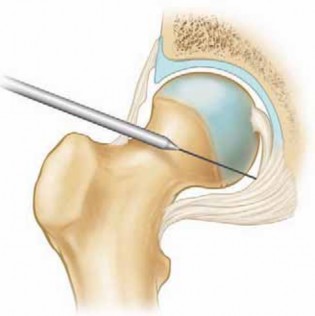

Arthroscopy of the intra-articular (“central”) compartment of the hip requires distraction.

1. Proper positioning is essential to the safety and efficacy of the procedure.

A well-padded perineal post should be secured against the ischium but lateralized against the medial thigh ( FIG 4A).

This keeps the post away from the pudendal nerve and aids in achieving the optimal vector for distraction.

Applying slight counter-traction to the nonoperative leg stabilizes the pelvis and keeps the post from shifting as traction is then applied to the operative leg.

The amount of abduction of the operative leg can be variable.

Less abduction may be necessary with a varus hip to make it possible to introduce the cannulas above the trochanter but enter the joint underneath the lateral lip of the acetabulum.

Neutral rotation during portal placement maintains a consistent relationship between the greater trochanter and the joint.

Slight flexion (10 degrees) relaxes the capsule and may facilitate distraction ( FIG 4B).

Excessive flexion should be avoided, because it can place tension on the sciatic nerve and reduce anterior access to the joint.

Most standard fracture tables can accomplish the positioning necessary for hip arthroscopy.

Specialized positioning devices are more practical for ambulatory surgery centers. These are more affordable and transportable, adapting to standard OR tables.

Arthroscopy of the peripheral compartment is performed with traction released and hip flexed ( FIG 4C).

Traction is released only after the instruments have been removed from the central compartment.

Flexion relaxes the capsule, opening the space within the periphery. Approach